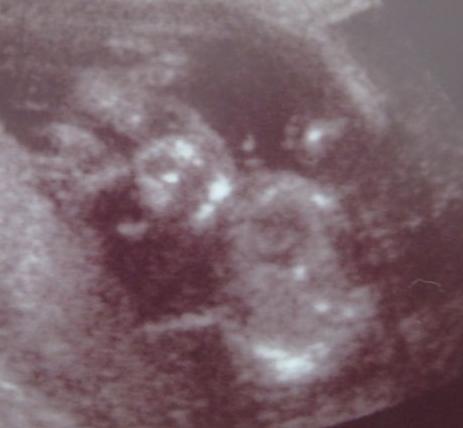

Akella nekem azért kellett az amnió.mert a 12.heti uh-n nagyobb volt a nyaki redő és a dokim egyből átküldött a genetikára ott négy féle vírusra vettek le vért és még javasolták az amniót,hogy 100%.ra mindent kizárjanak,én egyből igent mondtam mert nem akartam végig fosni hogy hátha tényleg baj van.Sajnos nálunk tényleg baj volt